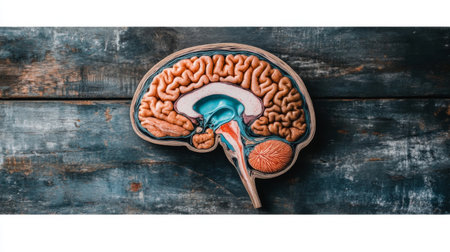

This detailed cross-section of the human brain illustrates its anatomical features, making it ideal for educational purposes in neuroscience and medicine.

An educational scene featuring a human brain cross-section with labeled parts, alongside medical charts and anatomical references for a classroom setting.

This image showcases a detailed model of the human brain, highlighting its unique anatomy. The brain model is displayed on a rustic wooden surface, ideal for educational and scientific use.

This close-up photo captures the intricate details and structures of a human brain, Cross-sectional image of a human brain, AI Generated

An educational scene featuring a human brain cross-section with labeled parts, alongside medical charts and anatomical references for a classroom setting.

An educational scene featuring a human brain cross-section with labeled parts, alongside medical charts and anatomical references for a classroom setting.